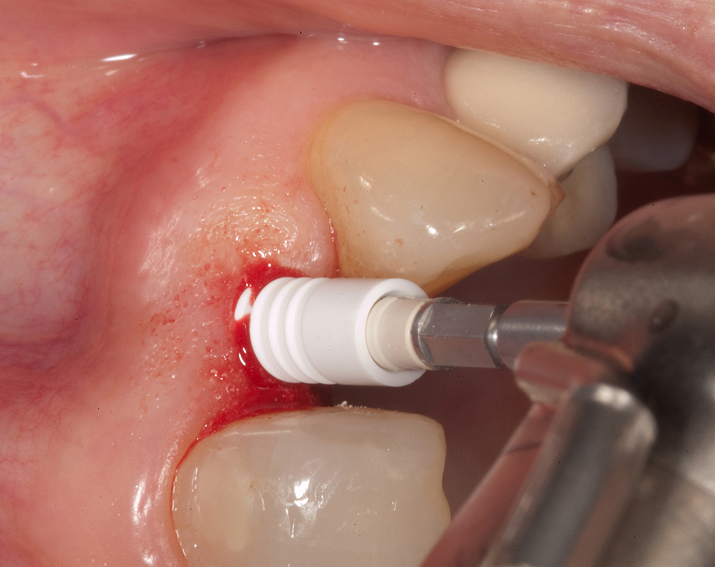

Zeramex T Implantat für Zahn 22

Ein Projekt aus dem Jahr 2013

Im vorliegenden Patientenfall musste der Zahn 22 nach erfolgloser Endodontie entfernt werden. Die Nachbarzähne waren kariesfrei, es wurde eine Marylandbrücke (eine Brücke mit zwei Flügelchen, die palatinal an den Nachbarzähnen verklebt werden) oder ein Implantat besprochen. Die Patientin hat sich für ein Vollkeramikimplantat entschieden. In der Diashow wird der operative Eingriff bis zur fertigen Krone gezeigt. Die Einheilzeit betrug drei Monate.